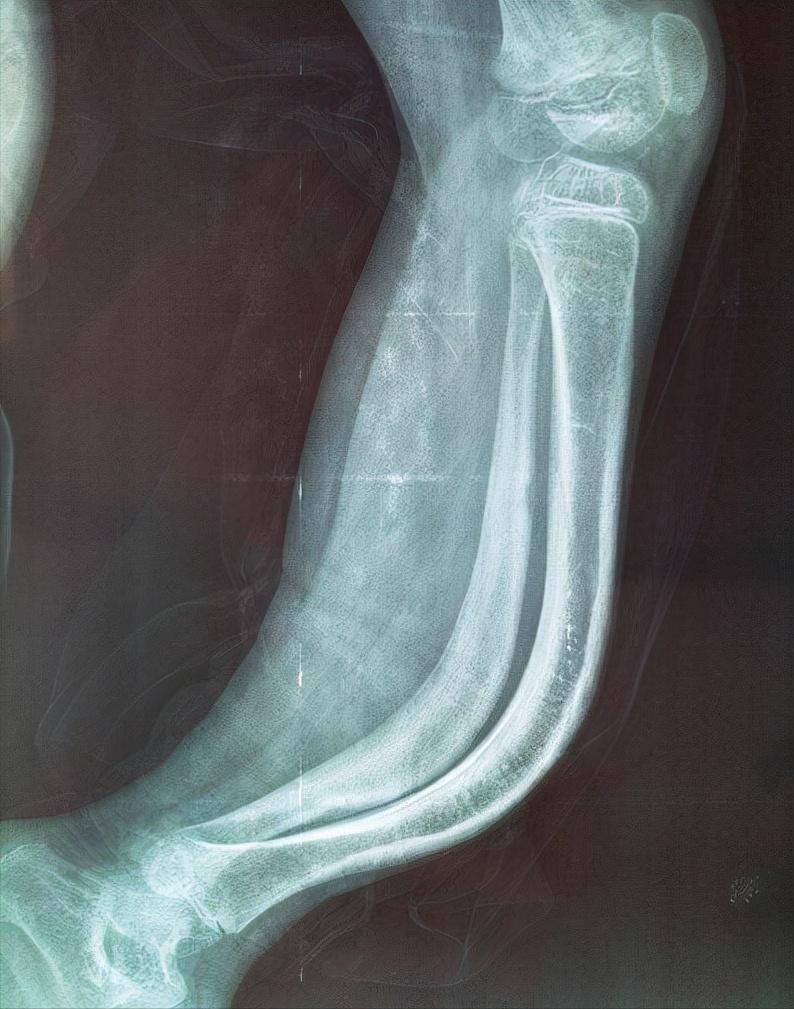

在他刚出生时,医生就发现李创利的右腿有些问题,检查之后发现他患有“成骨不全症”,意思就是骨头非常的脆弱,平时只要稍微一用力就可能会造成骨折或者骨裂,还检查出侏儒症,听完医生的话后李父坐在地上没有说话,李母则躺在病床上默默流泪。

李创利上节目时还讲过两个小时候的案例,在他还小的时候喜欢在院子里跑着玩,有次他从半米高的台阶上跳下去,就毫无预兆的瘫软在地,腿部骨头直接被折断,于是后来的他就不敢再跑来跑去的,只敢慢慢的走或者被父母抱着。

还有一次他躺在沙发上睡觉,爷爷看到后怕李创利着凉,连忙抱来一床薄被子给他加上,谁成想被子刚盖上,李创利一翻身胳膊和腿就全部骨折,这也让爷爷内心非常的愧疚,认为是自己给孙子带来的伤害,可李创利并没有怪爷爷,因为他已经习惯这样。